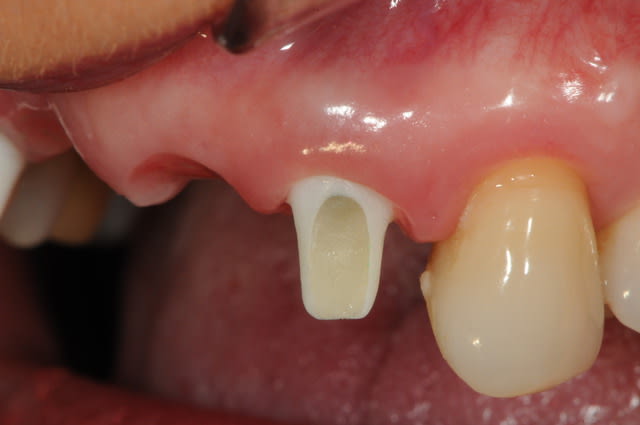

photo 1: j+1 mois et demi

la cigarette à repris de plus bel, je suis désespéré mais bon, avec la chir muco gingival je devrais y arriver.

photo 2: j+3 mois